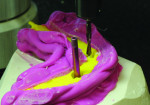

Temporary cylinders are then measured, cut, and screwed into place according to the guide pin paths and relieved denture base surface (Figure 25 and Figure 26).

The cut-back denture is then placed over the cylinders and into the matrix with guide pins screwed into place (Figure 27 and Figure 28) The denture is now relined, and the technician may attach temporary cylinders and create a convex intaglio surface (Figure 29 and Figure 31). Finally, the provisional implant-supported prosthesis is finished, polished, and delivered to the patient. (Figure 32 and Figure 33).